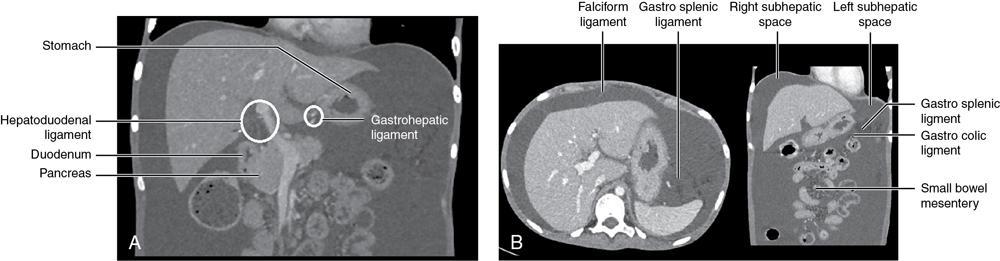

CROSS SECTIONAL ANATOMY OF ABDOMEN Satya Jha NORMAL ANATOMY OF ABDOMEN AND PELVIS Amandeep Singh The two major surfaces: The anterior and posterior layers of the coronary ligament converge on bare area (not covered by peritoneum). Its right and left margins form the right and left triangular ligaments. The right triangular ligament extends toward the diaphragm and separates right subphrenic space from right subhepatic space. The left triangular ligament gives tracts extending to the diaphragm and falciform ligament and does not compartmentalize the left subphrenic space. Ligamentum teres or the obliterated umblical vein is contained in falciform ligament which attaches the liver to anterior abdominal wall. The main portal vein, the proper hepatic artery and the common bile duct are contained within investing peritoneal folds of hepatoduodenal ligament at the porta hepatis (Fig. 7.2.2.1). Liver is divided into eight segments which are functionally independent and have their own vascular supply and biliary drainage. Arterial circulation: The branches of the hepatic artery accompanying the portal veins. Hepatic venous system: The right, middle, and left hepatic veins draining into IVC (Figs. 7.2.2.2 and 7.2.2.3). The gallbladder is a blind pear-shaped muscular membranous sac which is an embryologic derivative of the foregut, is a pouch lying along the undersurface of the liver. The gallbladder fossa is located in the plane of the interlobar fissure, which lies between the right and left hepatic lobes. Its major function is to store and concentrate bile which is produced by the liver. It measures approximately 4 cm in diameter when it is normally distended. Gallbladder is a smaller tubular structure in contracted state. The normal gallbladder wall thickness ranges from 1 to 3 mm. The gallbladder is divided into the fundus, body and neck. Infundibulum is present in the region of neck of the gallbladder, which is called the Hartmann pouch, where gallstones are usually impacted. Intrahepatic biliary radicles (IHBRs) scattered throughout the liver get confluent towards the hilum. They unite to form the right and left main hepatic ducts which further unite to form common hepatic duct (CHD) at the hilum. Common bile duct is formed by the union of cystic duct with common hepatic duct. The main pancreatic duct is joined with the common bile duct to form the ampulla of Vater at the major duodenal papilla (Figs. 7.2.2.4 and 7.2.2.5). Pancreas is located in anterior pararenal space of retroperitoneum anterior to perirenal (Gerota’s) fascia and posterior to parietal peritoneum. It is divided into head, uncinate process, neck, body and tail from right to left. Pancreas lies anterior to portal vein, which marks the point of transition between the body and neck. The region between head of pancreas and second and third parts of duodenum is known as the pancreatic groove. In postnephrectomy cases or with agenesis of kidney or ectopic kidney, pancreas moves posteriorly to partially fill in the empty renal fossa; its soft tissue density should not be mistaken for recurrent tumour. It is located in the pancreatic groove and is bounded superiorly by the duodenal bulb, laterally by second portion of duodenum, inferiorly by third portion of duodenum, medially by superior mesenteric vein and anterior to inferior vena cava. It is a wedge or wedge shaped lying posterior to superior mesenteric artery and vein. It is an imaginary junction between the head and body and lies directly over the junction of the splenic vein and superior mesenteric vein. It is located posterior to the lesser sac and anterior to the aorta, left adrenal gland, left kidney, and renal vessels and runs obliquely upward to the left of the superior mesenteric vessels. It is situated median to the colonic flexure and anterior to the left kidney. It is located in close proximity to the splenic hilum without a notable relation with the body of pancreas. It is seen anterior to the left kidney and median to the colonic flexure. The distal part of the tail passes between the peritoneal layers of the splenorenal ligament (Fig. 7.2.2.6 and 7.2.2.7).